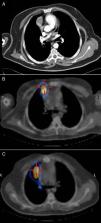

A la exploración física se presentaba asintomático. Los valores analíticos a destacar fueron: prolactina, 139ng/ml; testosterona total, 1,16ng/ml; testosterona libre, 3,41pg/ml; PTH, 2.112pg/ml; gastrina, >1.050pg/ml; calcio, 11,2mg/dl; fósforo, 2,82mg/dl. En la tomografía axial computarizada (TAC) se observaba una masa de 3cm de diámetro, sólida y con captación de contraste intravenoso, en el mediastino anterior en contacto con la pleura y el pericardio derecho junto a la aurícula homolateral, sin calcificación ni cavitación (fig. 1A). En la gammagrafía con octreótido que lo detectó se podían apreciar 2 lesiones nodulares con elevada densidad de receptores de somatostatina, una en hemitórax derecho y una segunda en la cola del páncreas. Se le realizó un SPECT-TC que confirmó la localización de ambas lesiones (fig. 1B).

Durante el seguimiento en consultas externas, se objetivó en el SPECT-TAC de octubre de 2007 un incremento de captación paramediastínica derecha (fig. 1C). La TAC confirmó la presencia de una consolidación de mediastino anterior con morfología seudonodular en contacto con la pleura y el pericardio derecho, próxima a la aurícula ipsilateral. En febrero de 2008 el paciente fue reintervenido mediante una toracotomía derecha sin visualizarse ni palparse ninguna nodulación, por lo que se resecó una parte de pericardio y área de fibrosis en la teórica localización sugerida por la captación de la gammagrafía. La anatomía patológica no evidenció neoplasia alguna, y el diagnóstico fue de fibrosis rádica. Actualmente el paciente se encuentra libre de enfermedad y sigue los controles oncológicos oportunos mediante la realización de TAC anual.